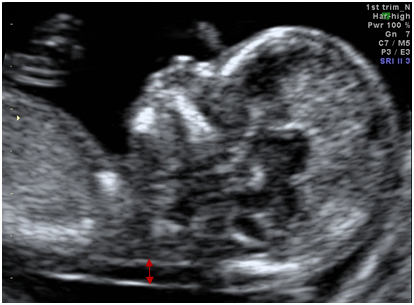

Показатели УЗИ плода с даунизмом

В процессе ультразвукового исследования, предпочтительно в конце первого триместра, специалист обращает внимание на показатели, указывающие на возможные генетические отклонения у плода.

УЗИ может выявить только явные анатомические патологии, поэтому не обеспечивает абсолютной точности в диагностике синдрома Дауна.

Признаки, вызывающие подозрения на синдром Дауна у плода:

- увеличение воротниковой зоны или наличие подкожной жидкости на задней части шейки эмбриона;

- недоразвитие носовых косточек (исследуется во втором триместре);

- значительное увеличение мочевого пузыря;

- уменьшение длины верхней челюсти;

- незначительная тахикардия.

Ниже представлено изображение УЗИ плода с синдромом Дауна, на котором отмечены отклонения от нормы.

При выявлении одного или нескольких настораживающих признаков беременной назначают дополнительные обследования для подтверждения или опровержения диагноза.